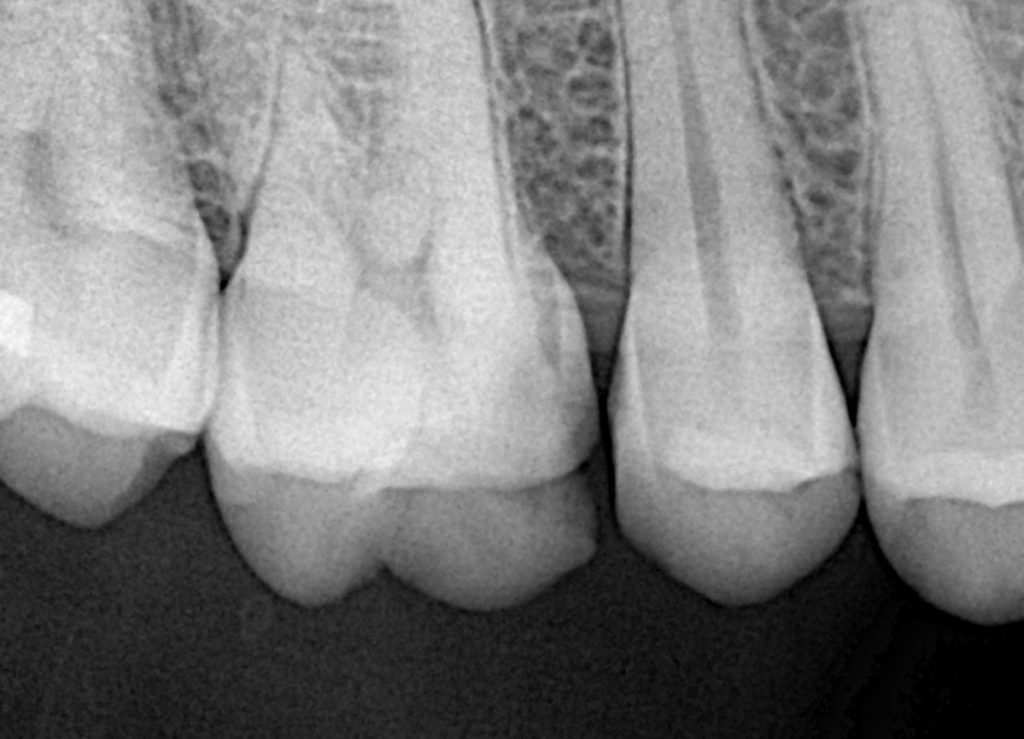

1. Pre-op evaluation

Bitewing radiographs show a small proximal radiolucency without pulpal involvement.

→ Perfect indication for a conservative Zerodont restoration.